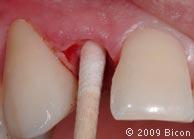

48. Очистка колодца имплантата ватным аппликатором, смоченным в спиртовом растворе.

49. Очистка колодца имплантата ватным аппликатором, смоченным в спиртовом растворе.